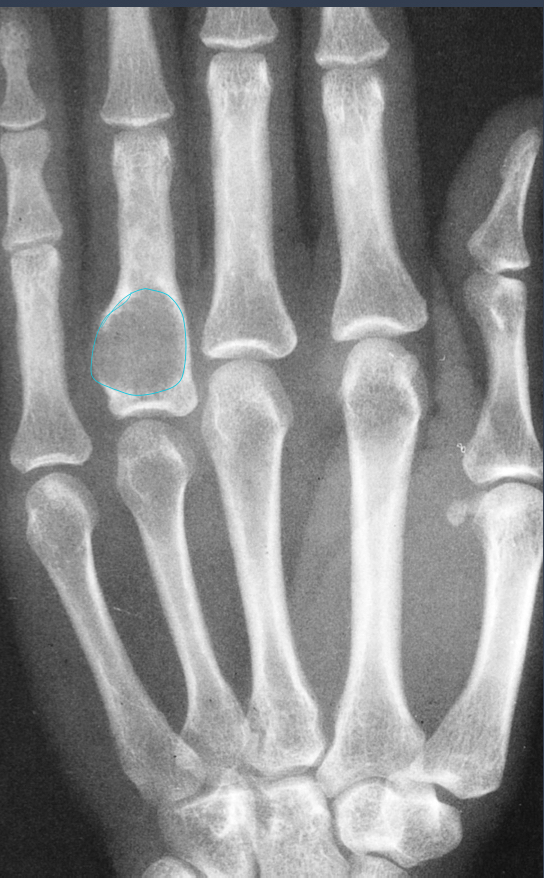

what is this?

MC age group?

enchondroma

10-30 yo